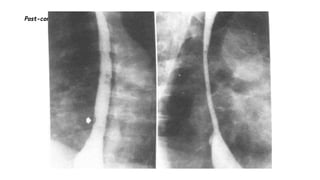

Post-corrosive stricture.